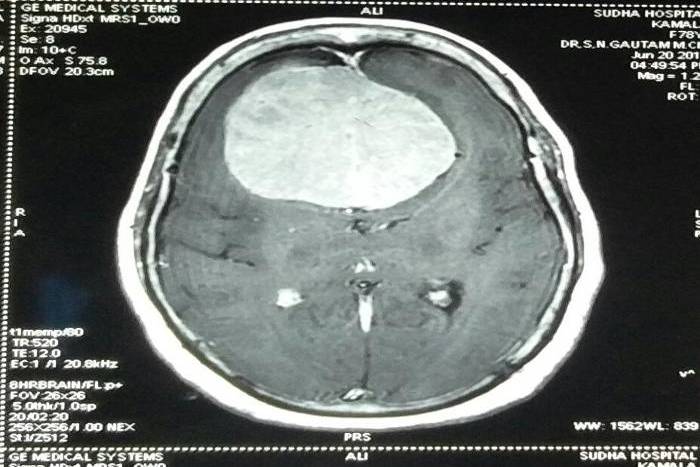

Doctor Remove 250 grams of lump from the woman's head in MBS Hospital Kota

एमबीएस अस्पताल में एक 70 वर्षीय महिला के सिर में से 250 ग्राम की गांठ निकाली। अस्पताल के न्यूरोसर्जन डॉ. एसएन गौतम ने छह घंटे चली सर्जरी के बाद मस्तिष्क में से ठोस गांठ को निकाला।

डॉ. गौतम का कहना है कि उन्होंने इतनी बड़ी साइज की गांठ की सर्जरी पहली बार की है। गांठ का वजन 250 ग्राम और आकार 10 गुना 10 सेंटीमीटर का था। जिसे दूरबीन से सर्जरी में टूकड़े-टूकड़े कर निकाला। इस दौरान महिला को तीन यूनिट रक्त भी चढ़ाया गया। सर्जरी में एनेस्थिसिया विभाग की डॉ. उषा दरिया और डॉ. अनुभव ने सहयोग किया। मरीज की स्थिति में लगातार सुधार हो रहा है। उसे आईसीयू से पोस्ट ऑपरेटिव वार्ड में शिफ्ट किया गया है। साथ ही गांठ की बायप्सी जांच के लिए पैथोलॉजी विभाग में भेजा है।

डॉ. गौतम ने बताया कि यह महिला कुछ माह से सिर में दर्द, उल्टी, चलने फिरने में परेशानी, असामान्य व्यवहार और पेशाब पर नियंत्रण खत्म होने की शिकायत लेकर आई थी। महिला की जांच कराने पर उसके दिमाग के अगले हिस्से के बीचों बीच एक गांठ होने का पता चला। वे रिपोर्ट में इतनी बड़े ट्यूमर को देख चौक गए। सर्जरी में भी महिला की उम्र ज्यादा होने और गांठ बड़ी होने से खतरा था। उसके परिजनों को गांठ की प्रकृति और उससे जुड़े खतरों के बारे में बताया और वे सर्जरी के लिए तैयार हुए।